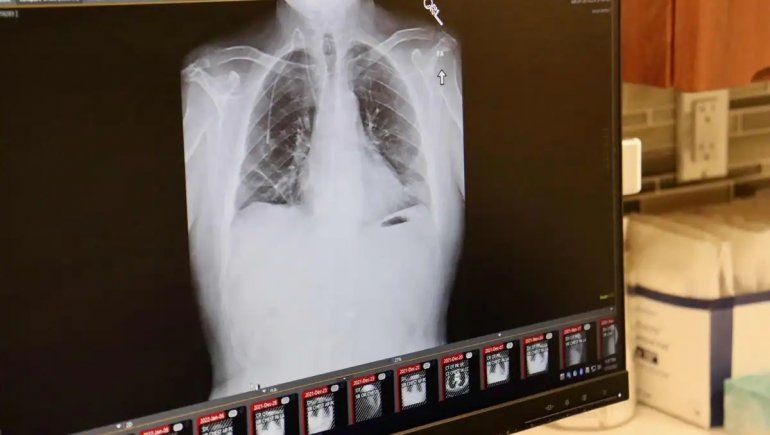

Médicos estadounidenses anunciaron este jueves que realizaron con éxito un doble trasplante de pulmón, un procedimiento “extremadamente poco común”, según calificaron, en un paciente con cáncer terminal, lo que abre nuevas esperanzas a otros que están en etapas avanzadas de la enfermedad mortal.

“El trasplante de pulmón para el cáncer de pulmón es extremadamente poco común y se han informado pocos casos”, dijo en un comunicado Ankit Bharat, jefe de cirugía torácica del Northwestern Medicine en Chicago, institución donde el pasado 25 de septiembre se llevó a cabo la cirugía en un hombre identificado como Albert Khoury, un no fumador de 54 años.

Bharat explicó que “para los pacientes con cáncer en etapa 4, el trasplante de pulmón se considera un completo ‘no-no’”, en referencia a las escasas chances de tener éxito. “Debido a que el cáncer de Albert estaba alojado solo en el tórax, estábamos seguros de que podíamos eliminarlo todo durante la cirugía y salvarle la vida”, aseguró. Seis meses después de la cirugía, que duró siete horas, “los pulmones están funcionando bien y no tiene signos de cáncer en su cuerpo”, consignó el especialista.